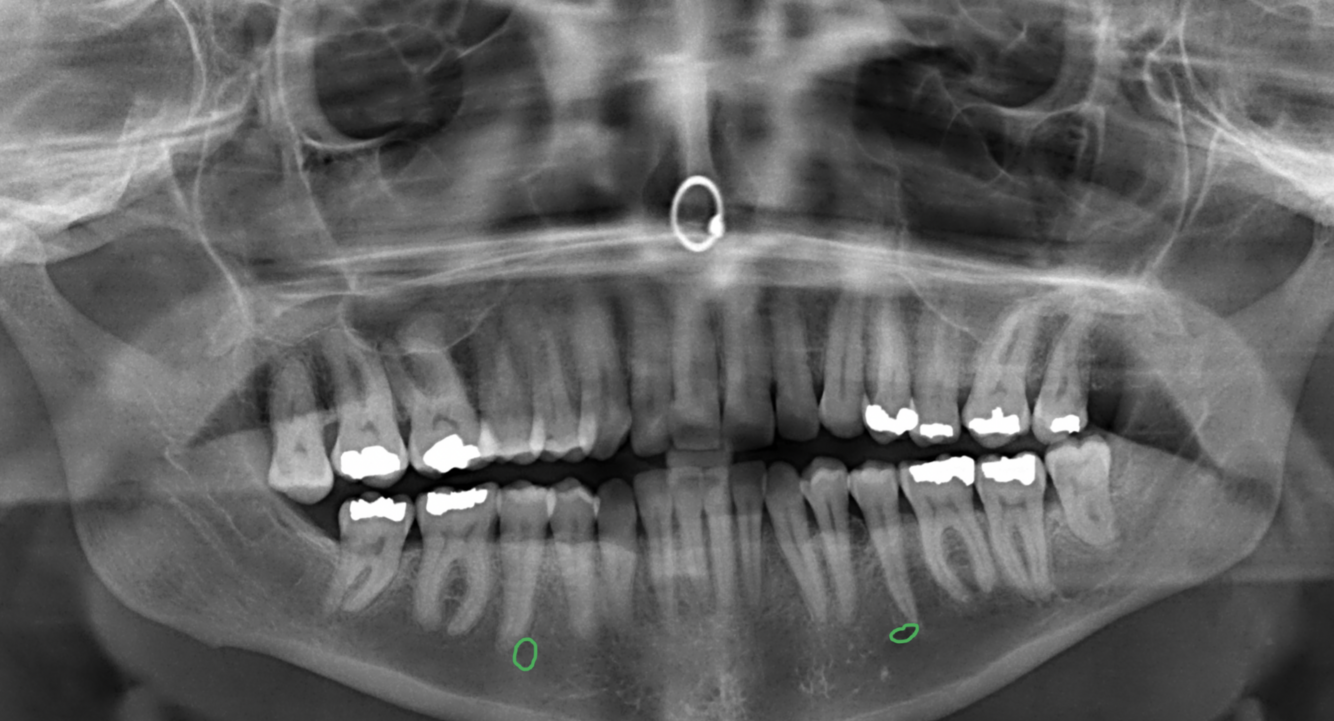

13

Label the following image:

A

A: maxillary sinus

B: mandibular canal

C: internal oblique ridge

D: genial tubercle & lingual foramen

E: submandibular fossa

F: zygomatic process

G: nasal septum

H: anterior nasal spine